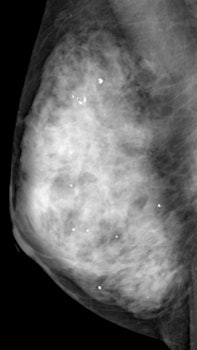

Mammography is the only proven method of screening that reduces mortality, but it is inaccurate in dense breasts, Ohuchi and colleagues wrote. In Asia, where women characteristically have dense breast tissue, age-specific breast cancer incidence peaks in the younger age group of 40 to 49, compared with women 60 to 70 years old in Western countries.

Adding ultrasound to mammography screening detects more early invasive breast cancer and probably reduces mortality, according to a 4 November study in the journal Lancet. The Japanese trial is thought to be the first of its kind in a large randomized multicenter population, and that focused on younger women at average risk with dense breast tissue.